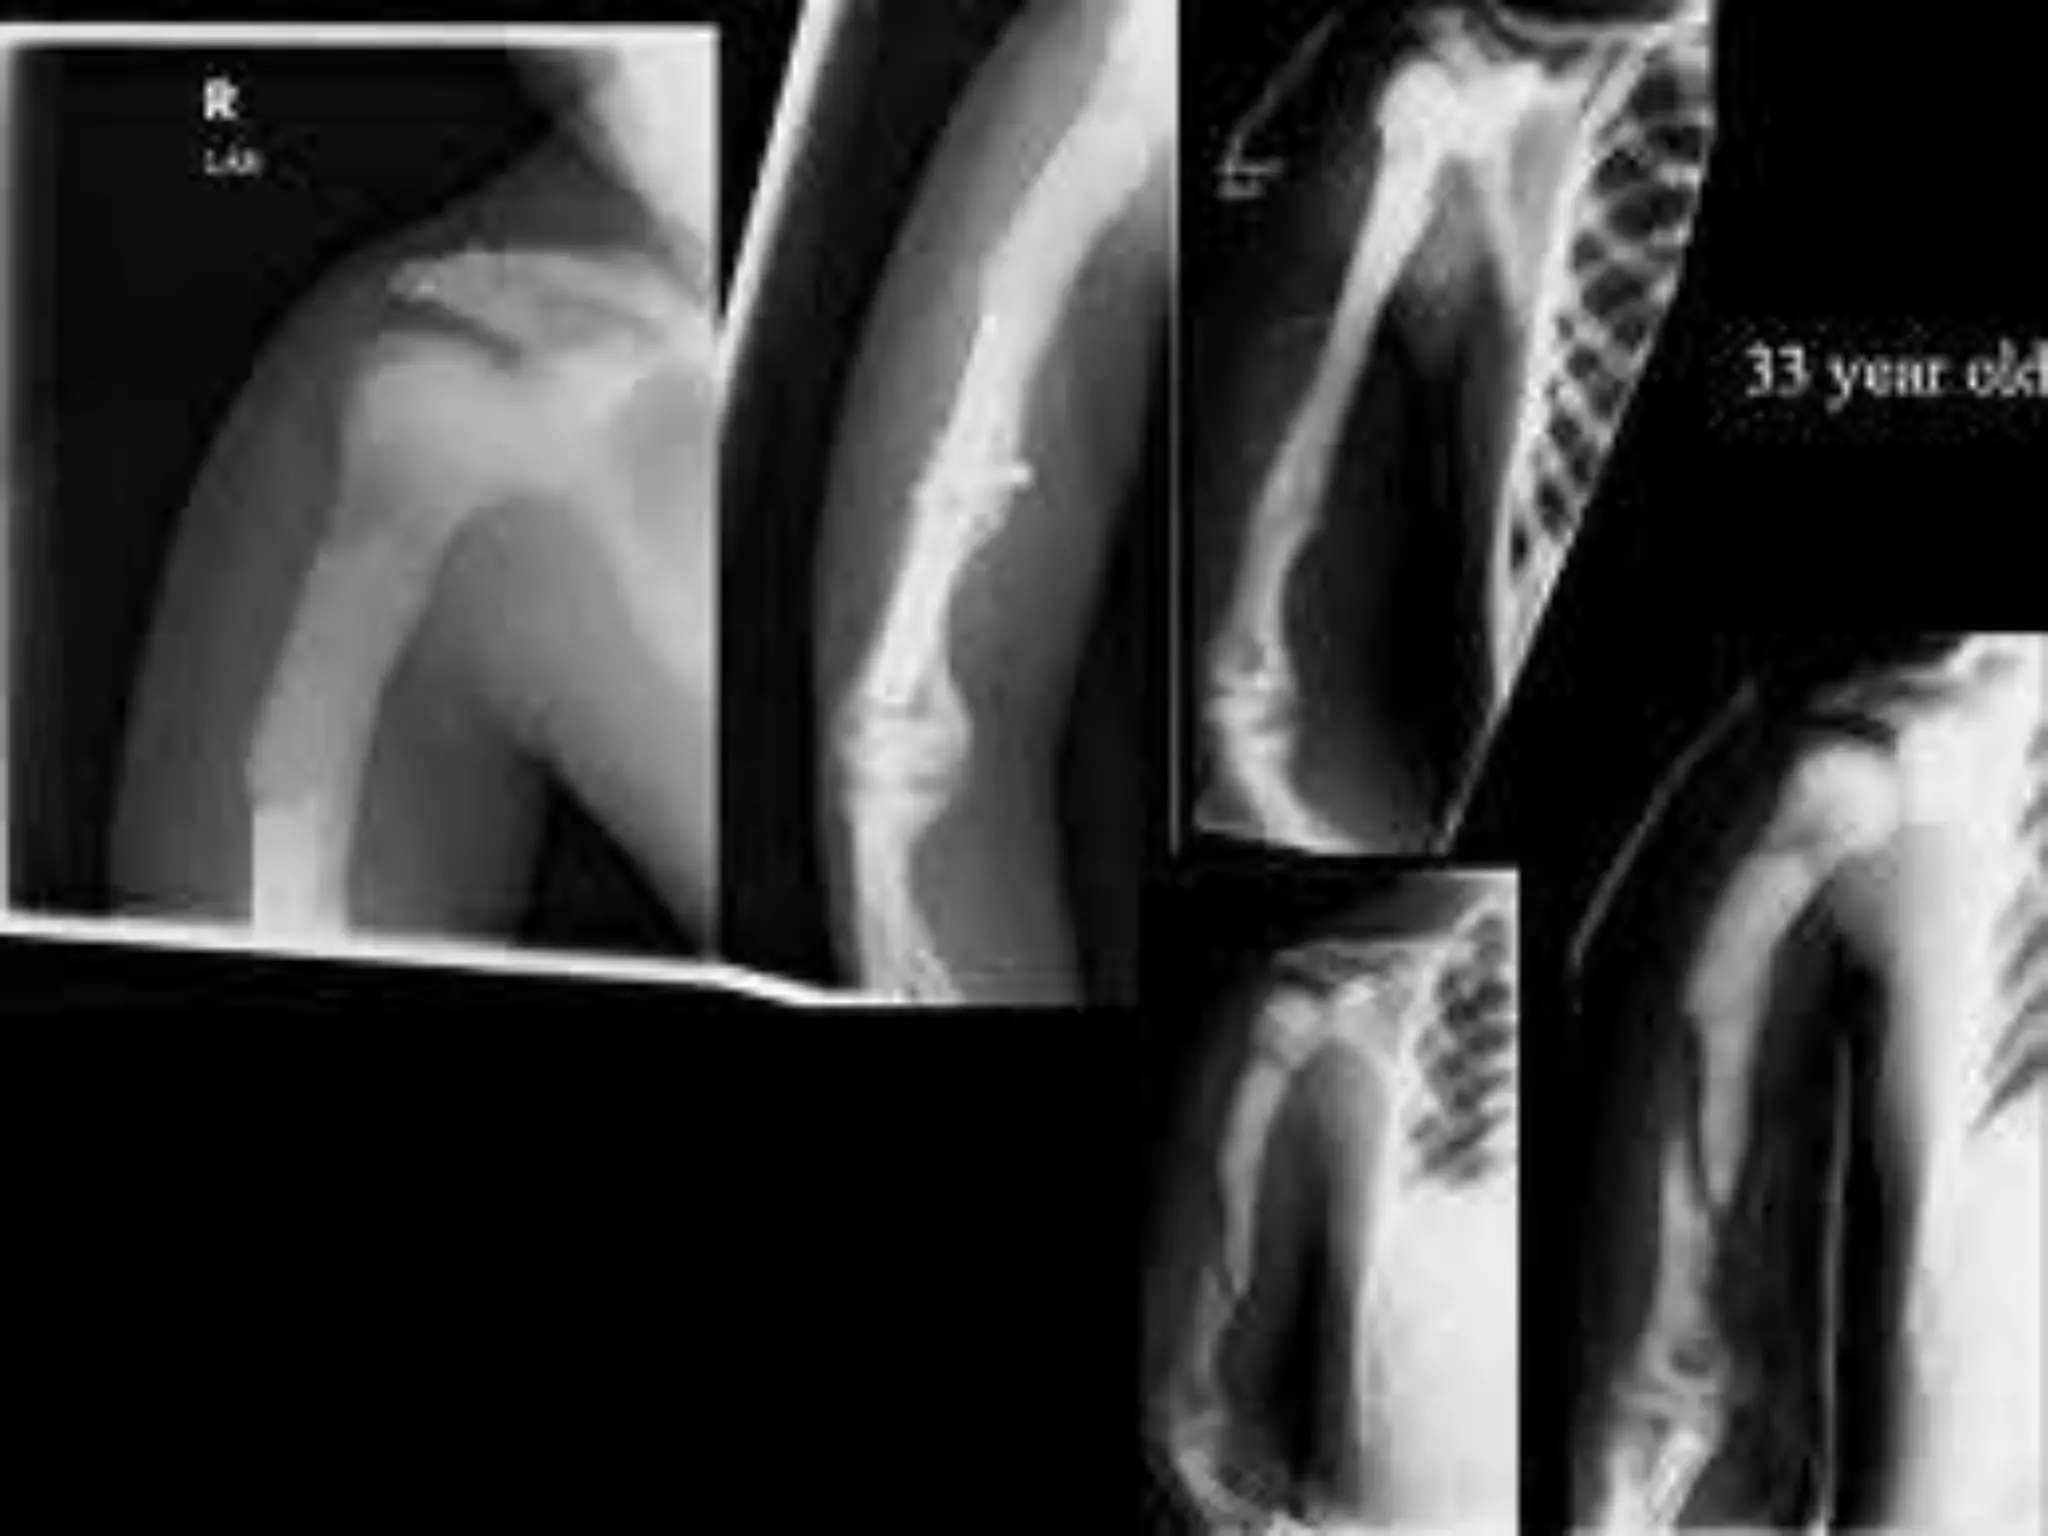

FIBRODYSPLASIA OSSIFICANS PROGRESSIVA

(MYOSITIS OSSIFICANS PROGRESSIVA)

Characterised by ossificans of muscle connective

tissue (trunk mostly)

Starts with fever & inflammation in early childhood

Associated : shortening of big toe & thumb

FIBRODYSPLASIA OSSIFICANS PROGRESSIVA (MYOSITISOSSIFICANS PROGRESSIVA) Characterised by ossificans of muscle connective tissue (trunk mostly) Starts with fever & inflammation in early childhood Associated : shortening of big toe & thumb